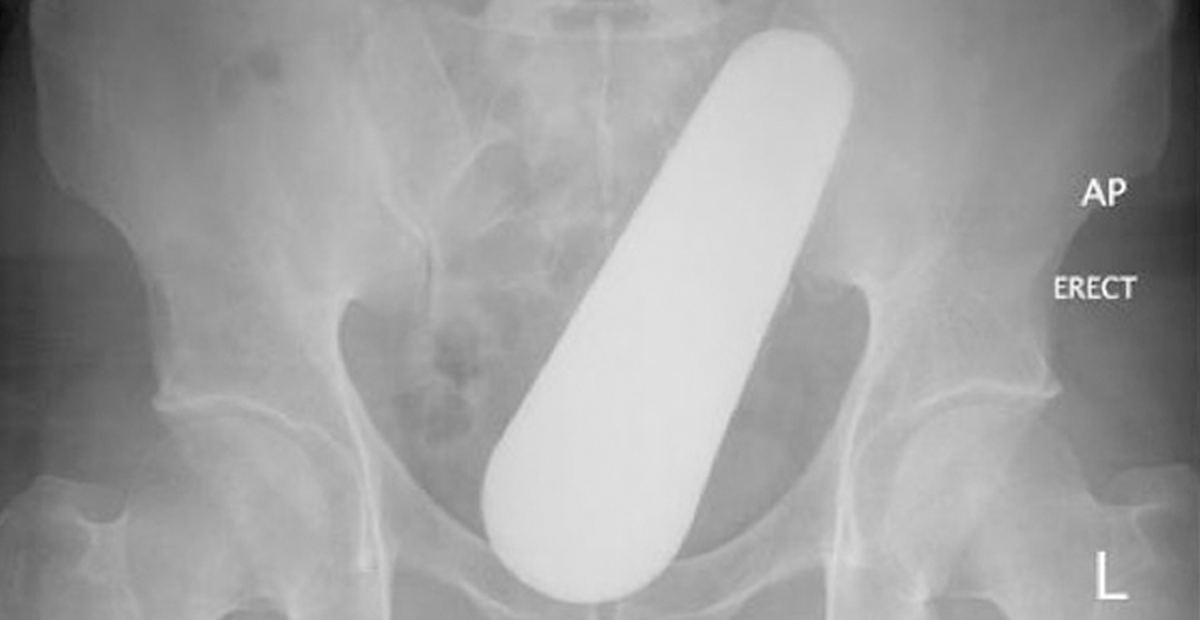

SE INTRODUCE OBJETO EN EL RECTO Y ACABA EN ÁREA DE URGENCIAS

n hombre joven, llegó a la Clínica 79 del Instituto Mexicano del Seguro Social de Piedras Negras presentando fuertes dolores en el...